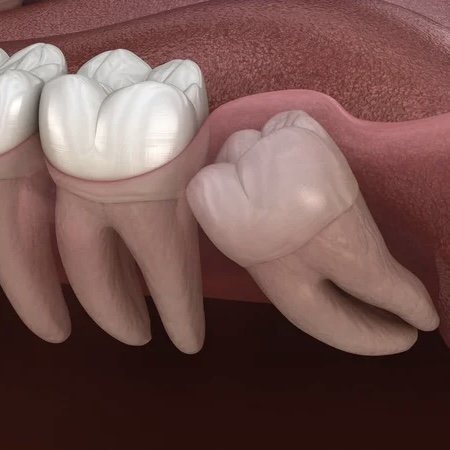

- ▪ дистопією та ретенцією – порушенням розташування, неповним прорізуванням

- ▪ тиском на сусідні сьомі зуби із руйнуванням останніх

- ▪ дистопія, коли восьмий зуб тисне на сьомий і «лежить» горизонтально

Якщо зуб мудрості починає тиснути на сусідній сьомий, може зміщуватись весь зубний ряд. В результаті передні зуби викривляються і порушується прикус. Це також є прямим показом до виривання.